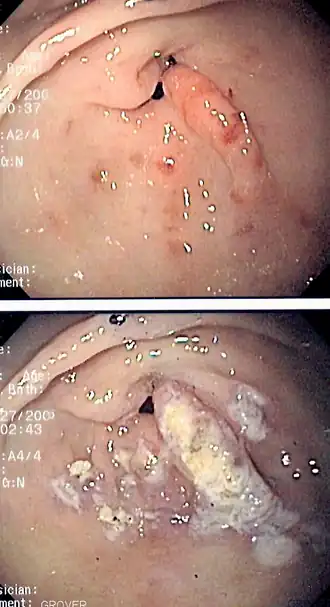

![]() Imagen de endoscopia de la ectasia vascular antral gástrica vista como un patrón radial alrededor del píloro antes (arriba) y después (abajo) del tratamiento con coagulación con plasma de argón. | ||

La GAVE suele diagnosticarse de forma definitiva mediante una biopsia endoscópica .[10][11][14][21] Las rayas de sandía reveladoras aparecen durante la endoscopia.[10]

La GAVE se trata comúnmente por medio de un endoscopio, incluida la coagulación con plasma de argón y electrocauterio.[11][10][22] Dado que la endoscopia con fotocoagulación con argón es "generalmente efectiva", la cirugía "generalmente no es necesaria".[10] La terapia de coagulación es bien tolerada pero "tiende a inducir supuración y sangrado".[10] La "endoscopia con ablación térmica" es el tratamiento médico preferido debido a sus bajos efectos secundarios y baja mortalidad, pero "rara vez es curativa".[11] El tratamiento de la GAVE puede clasificarse en endoscópico, quirúrgico y farmacológico. El tratamiento quirúrgico es definitivo, pero rara vez se realiza hoy en día con la variedad de opciones de tratamiento disponibles. Algunas de las modalidades comentadas se han utilizado en pacientes con GAVE con otra enfermedad subyacente. El tratamiento sintomático incluye la administración de suplementos de hierro y la transfusión de sangre para los casos con anemia grave, los inhibidores de la bomba de protones pueden mejorar la gastritis crónica de fondo y las erosiones diminutas que suelen coexistir en los informes de las biopsias.